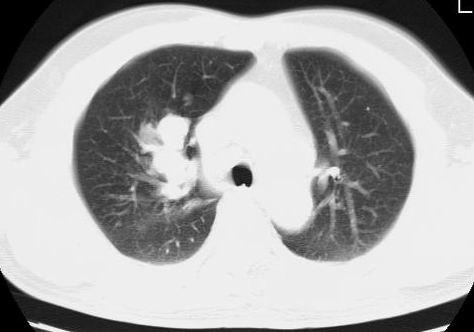

标题: CT15869:男性,71岁,因咳嗽而就诊,请讨论右上肺病变性质 [打印本页]

标题: CT15869:男性,71岁,因咳嗽而就诊,请讨论右上肺病变性质

患者,男性,71岁,因咳嗽而就诊,

典型的右肺中心性肺癌并纵隔淋巴结转移

右肺中心性肺癌并纵隔淋巴结转移可能性大!

病灶中等程度强化 还是支持肺癌诊断

考虑右肺中心性肺癌并右肺门及纵隔淋巴结转移。

1,右肺中心型ca,气管隆突旁淋巴结转移。

2,右膈明显抬高,建议肝脏扫描排除转移或原发灶。